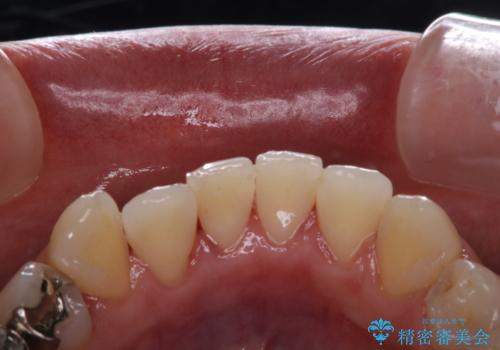

歯科衛生士によるPMTCでお口のケア

- 歯医者に来院することが久しぶりで、まずはクリーニングを希望とのことでした。コースや内容は、一番状態に合ったものでとのことだったため、PMTC60分コースを行いました。

PMTCとは「Professional Mechanical Tooth Cleaning」の略で、専用の機器を使った歯のクリーニングです。

PMTCは誰もが実施できるというわけではなく、歯科医師や歯科衛生士によるプロフェッショナルケアです。